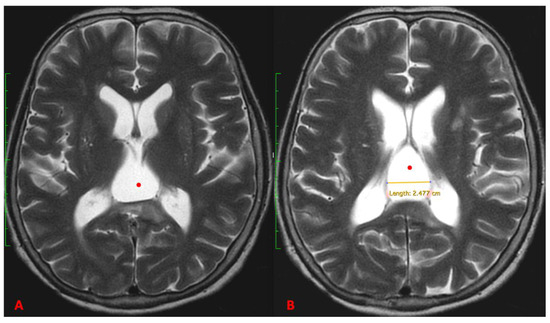

2. Case Report

3.2. Imaging

- T1-Weighted Images: Midline cysts typically appear hypointense (dark) on T1-weighted images.

- T2-Weighted Images: These cysts usually appear hyperintense (bright) on T2-weighted images, reflecting their fluid content.